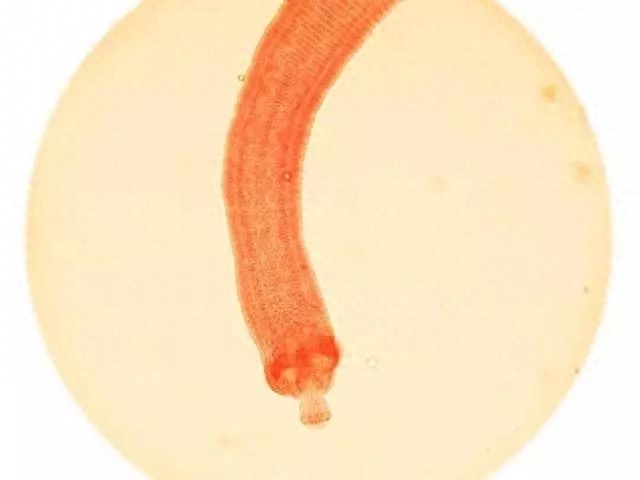

10.绦虫

700人

科学家对寄生虫的研究发现,绦虫会引起一种叫做囊虫病的感染。每年大约有700人死于这种感染。